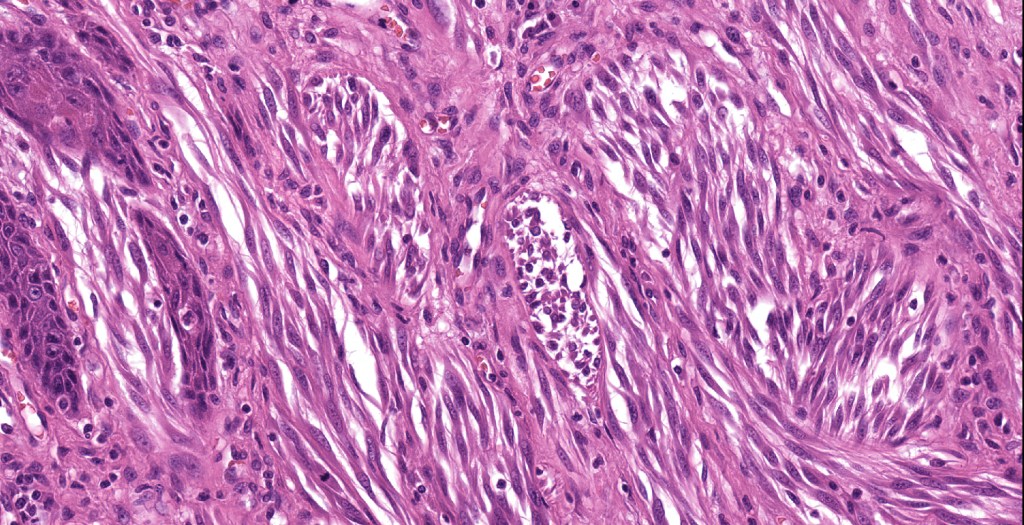

•Junctional nests often vertically orientated, dyscohesive with a surrounding retraction artifact

•Pleomorphism is almost invariable but affects all of the population to the same extent i.e., the cells & nuclei all look very much the same

•Spindle cell nests often display a “raining down” growth pattern

•Spindle cells have abundant cytoplasm and vesicular nuclei with small nucleoli

•Epithelioid cell variants often show greater pleomorphism and cells can frequently appear bizarre with abundant, sometimes ground glass cytoplasm and large vesicular nuclei with prominent eosinophilic nucleoli, multinucleate cells are often seen

•Intracytoplasmic pseudoinclusions commonly present in epithelioid cells